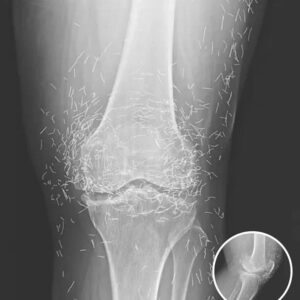

Doctors Stunned After Looking At This X-Ray Of Woman Suffering Joint Pain

A routine X-ray of a 65-year-old South Korean woman with severe knee pain revealed hundreds of tiny gold needles embedded in her tissue. She had turned to…